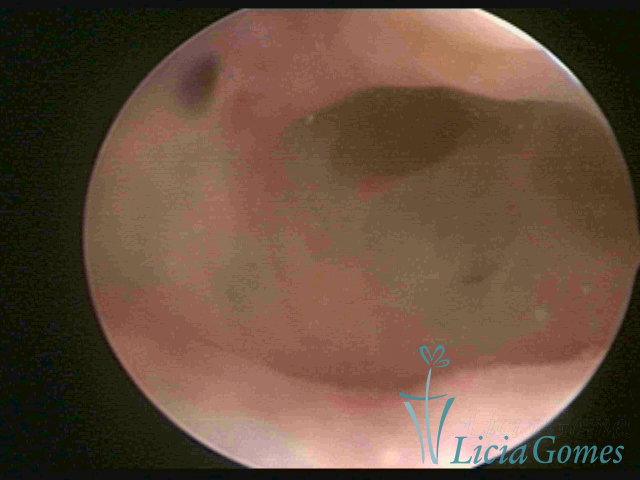

ADENOMIOSE

É a presença de tecido endometrial na camada muscular do útero

A vídeo-histeroscopia permite diagnosticar às lesões próximas às camadas miometriais superficiais, próximo ao endométrio visualizando lesões de coloração violácea, circunscritas, ou acastanhadas com conteúdo achocolatado.